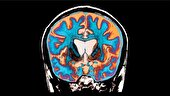

رئیس پژوهشکده سرطان معتمد گفت: فرآیند تولید ویروس برای درمان سرطان را پشت سر گذاشتهایم، تستهای آزمایشگاهی و مطالعات حیوانی را با موفقیت به پایان رسانده و وارد فاز یک انسانی شدهایم.